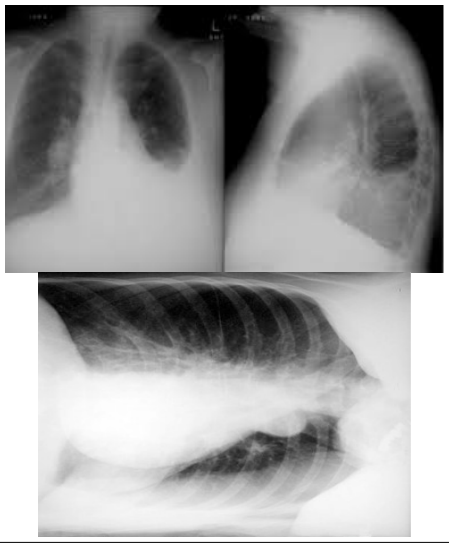

Paciente do sexo masculino, de 69 anos, procura atendimento por perda de peso, 15 kg, em seis meses, hiporexia, sudorese, tosse seca, febre não aferida vespertina, e dispneia aos pequenos esforços progressiva. Procurou atendimento prévio e foi prescrito antibiótico, amoxacilina/clavulanato 875 mg/125 mg, que fez uso por dez dias. Nega melhora dos sintomas. Tabagista, 60 maços/ano. Nega outras patologias ou uso de medicações contínuas. Ao exame, apresenta-se em regular estado geral, eupneico, saturação de oxigênio 95% ar ambiente, frequência cardíaca: 90 bpm. Foram solicitados exames para avaliação, conforme apresentado a seguir: Hemograma: hb 11,0, leucócitos 11.000, bastões 2%, neutrófilos 60%, plaquetas 235.000. PCR 10. Raio X de tórax:

Após a conduta inicial foi realizado toracocentese diagnóstica apresentando:

Líquido pleural: serosanguinolento, pH: 7,40, hemácias maior 1.000.000/mm³, glicose 30 mg/dl, DHL: 400 IU/l, proteína 3,0 g/dl, ADA 35 U/l, citologia oncótica positiva, BAAR negativo. Sangue: glicose: 180 mg/dl, DHL: 450 IU/l, proteínas 3,8 g/dl.

Nesse caso, qual diagnóstico provável para esse paciente?